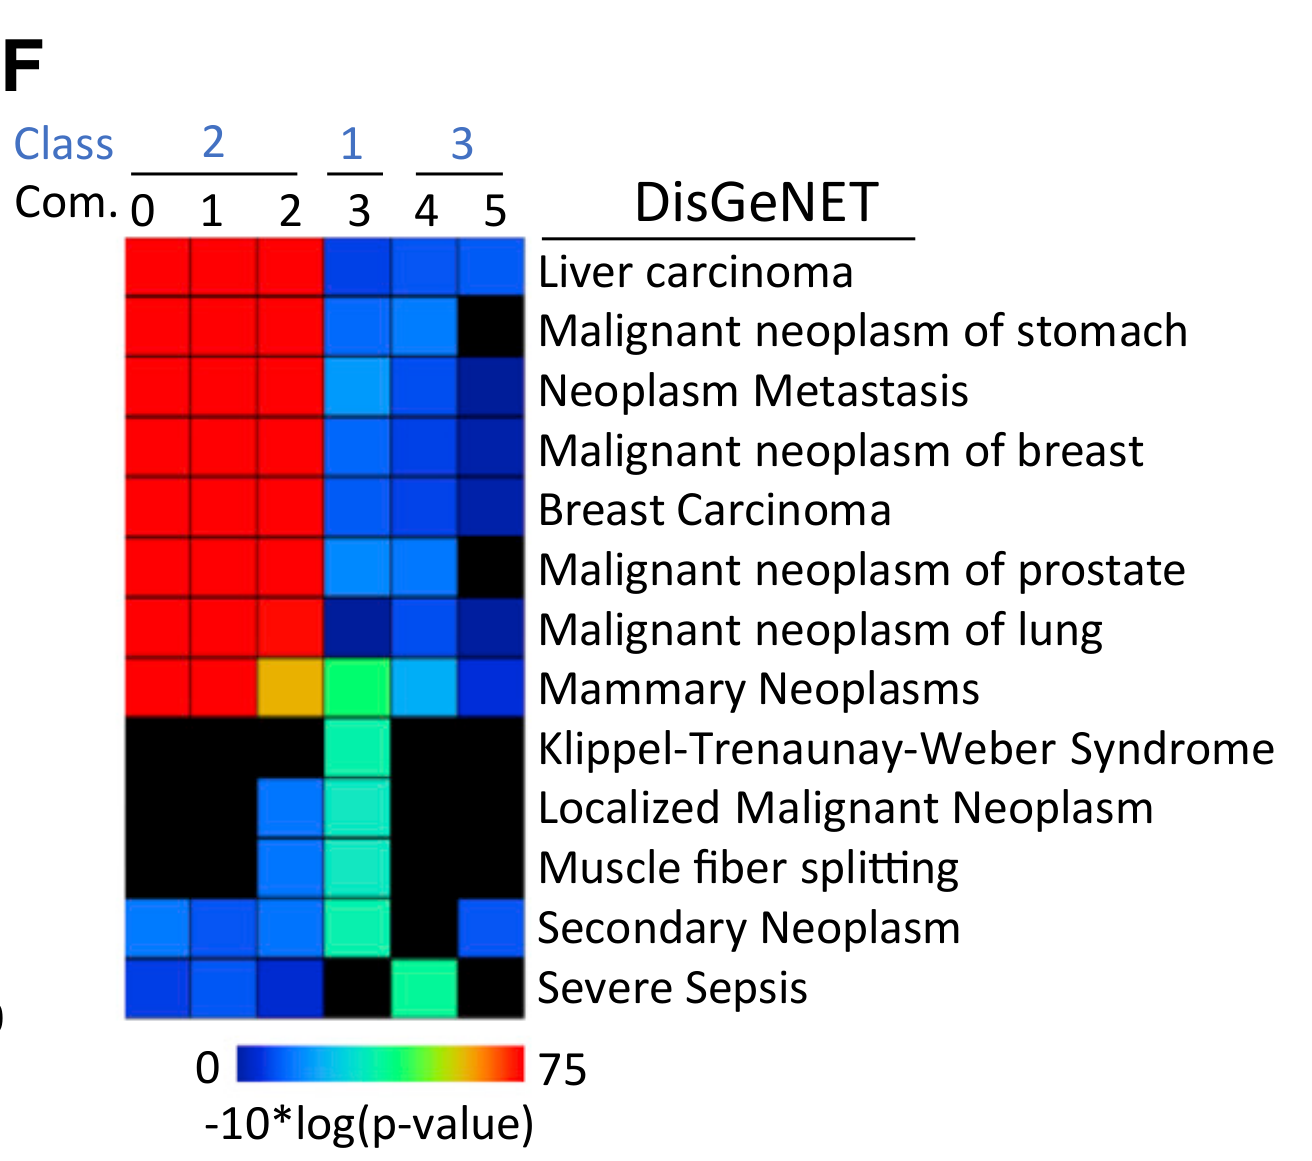

Aggarwal B. and Sinha S. - 2025

CellSP enables module discovery and visualization for subcellular spatial transcriptomics data

Condition Dimension

N/A

Data Components

Evaluation metrics

Data

Modality

Imaging-based

Resolution of observation

Sub-cellular

Visualized Elements

FeatureObservation

Biological

CellularMolecularTissue

Abstraction

None

Chart Type

ScatterplotSpatial Gene Expression Map

Communicative/Contextualization

AnnotationHighlighting

Comparative Design

None

Layout

Spatial : Physical

What is the raw visual evidence for the subcellular localization of the module genes within individual cells?